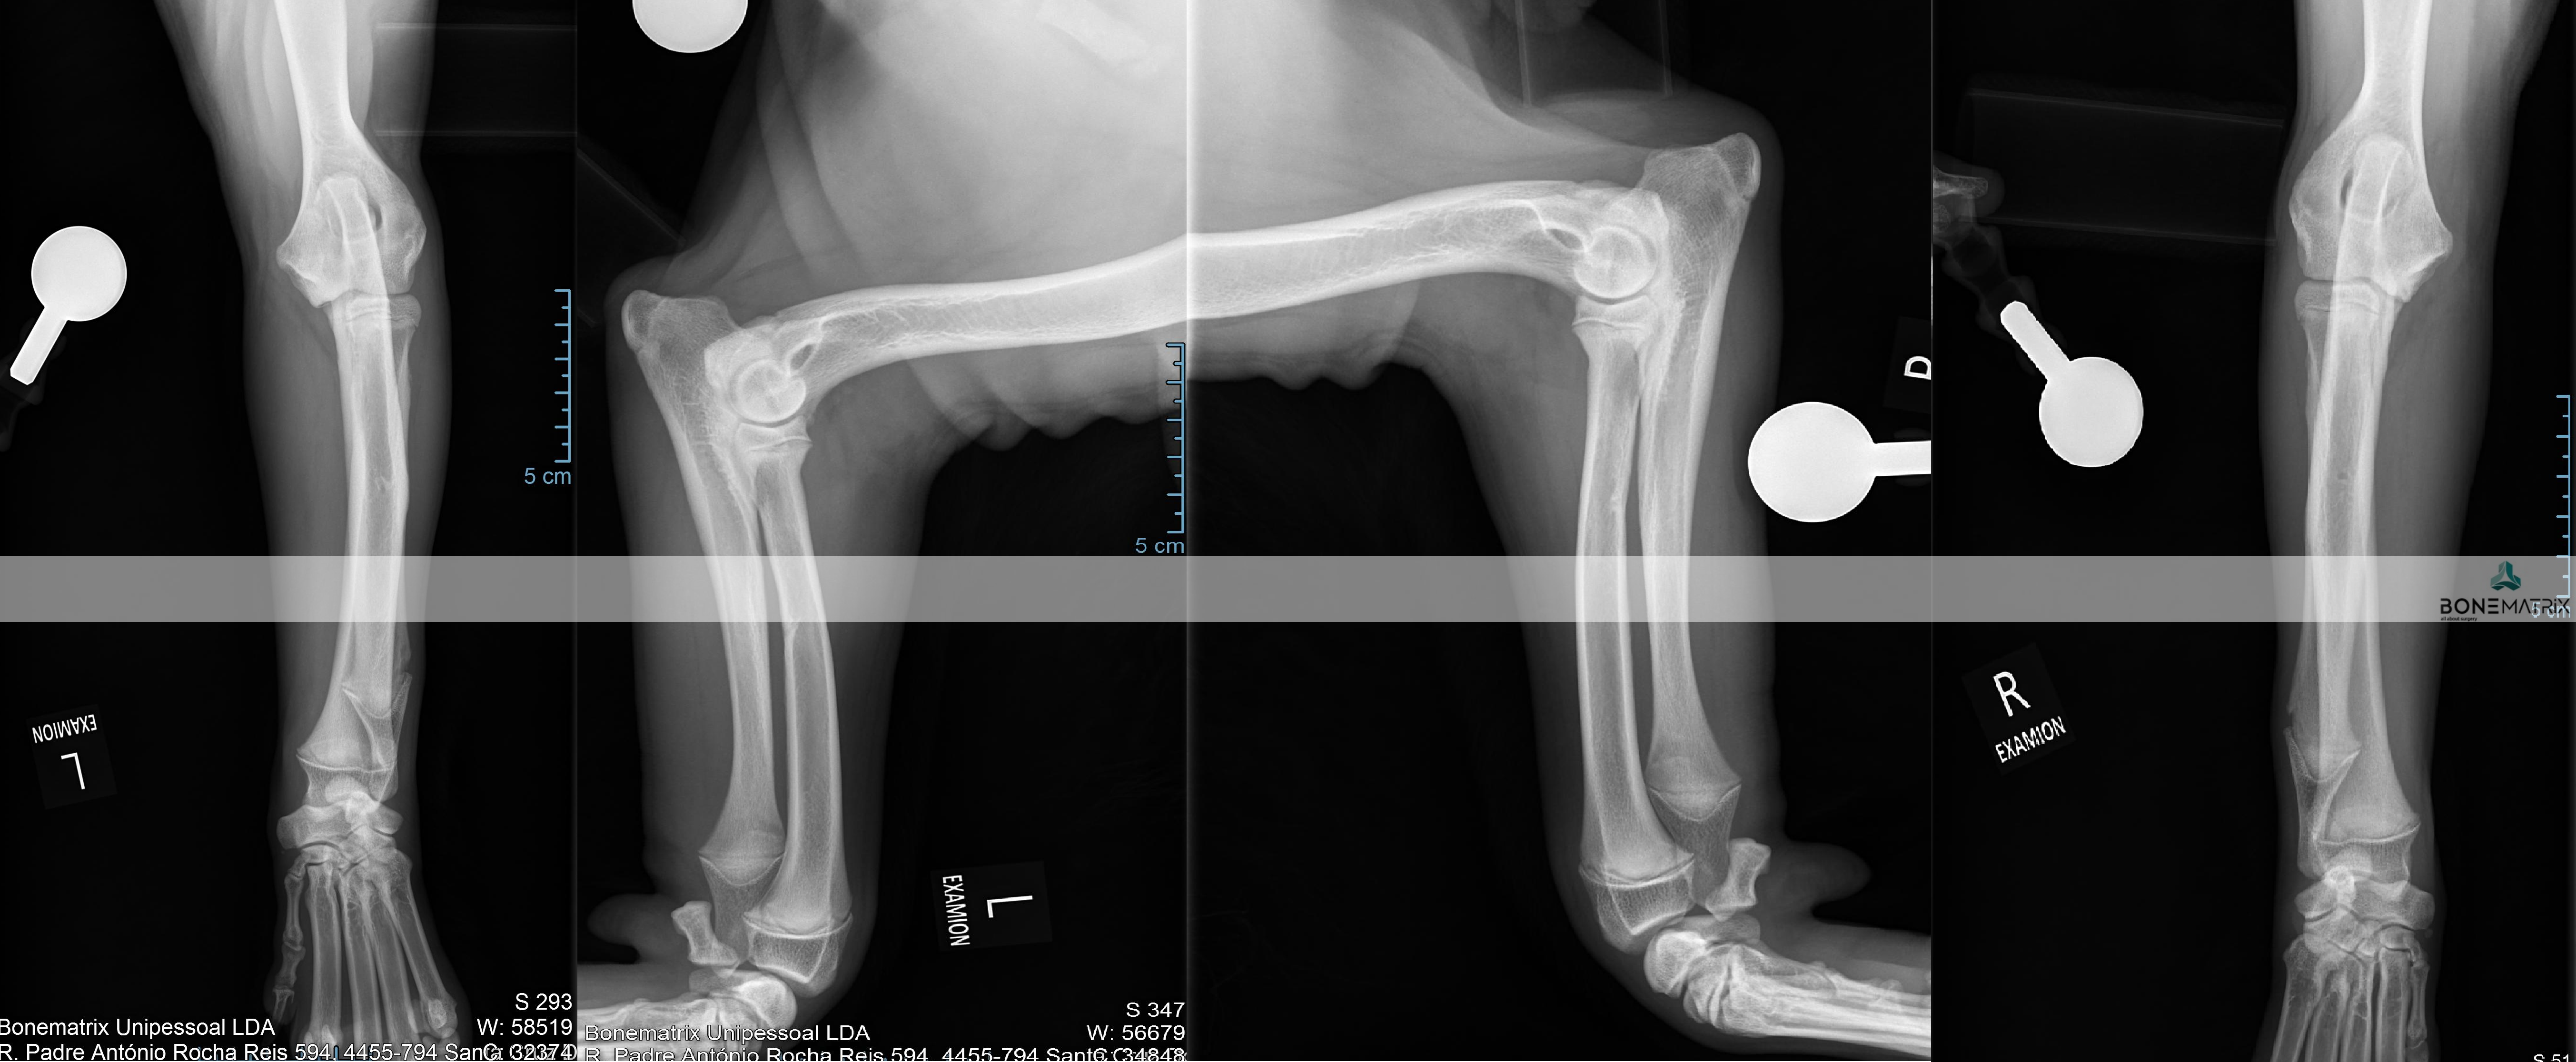

O que é?

As deformidades angulares são patologia que podem assumir as mais variadas apresentações.

A sua origem pode estar relacionada com fatores genéticos, traumas sofridos durante a imaturidade do animal, pode apresentar-se como uma doença de desenvolvimento e pode também ter influências ambientais ou nutricionais.

Todas elas se caracterizam-se por um desvio na correta forma de um determinado osso ou membro.

Que consequências podem surgir da apresentação de uma deformidade angular?

As consequências da apresentação de deformidades angulares estão em muito relacionadas com a localização destas e com a exuberância da apresentação.

Estes desvios da conformação normal podem provocar desde osteoartrite articular ou laxitude dos mecanismos de estabilização de articulações até incapacidade na realização da marcha do animal afetando severamente a qualidade de vida deste.

O diagnóstico é realizado por meio de análise clinica da anatomia dos membros e é estudada por norma através da realização de um estudo radiográfico.

O animal poderá ser desde assintomático a apresentar sintomas que passam por claudicação, lesões em estruturas articulares consequentes destes desvios angulares, incapacidade na realização de determinados movimentos até incapacidades severas de mobilidade.

A realização de um estudo radiográfico é imprescindível para definição de um planeamento cirúrgico de correção.

Em casos mais complexos pode ser necessário o recurso a estudos de imagem avançada, tanto para o estudo da deformidade como para a produção de instrumentos de cirurgia (guias de corte 3D, produção de placas com customizadas) para que seja realizada a cirurgia com precisão.

O tratamento depende sempre da forma da patologia apresentada.

Por norma envolve realização de cortes ósseos, definidos com determinada angulação para que seja corrigida a deformidade angular, com subsequente estabilização da fratura induzida com a utilização de placas e parafusos bloqueados (sistema que oferece a maior segurança para a estabilização de fraturas).